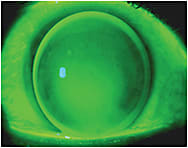

Figure 3. Status post-radial keratotomy.

Normal corneas have a prolate shape, but after refractive corneal surgery for myopia, the central ablation zone produces a central flatter corneal region surrounded by an area of steeper peripheral cornea (Figure 3). A sunken corneal transplant graft may have a similar shape. If there is post-surgical residual irregular astigmatism that requires a GP lens, this now oblate cornea is often better fit with a reverse geometry design to prevent excessive central corneal clearance with disproportionate midperipheral bearing.